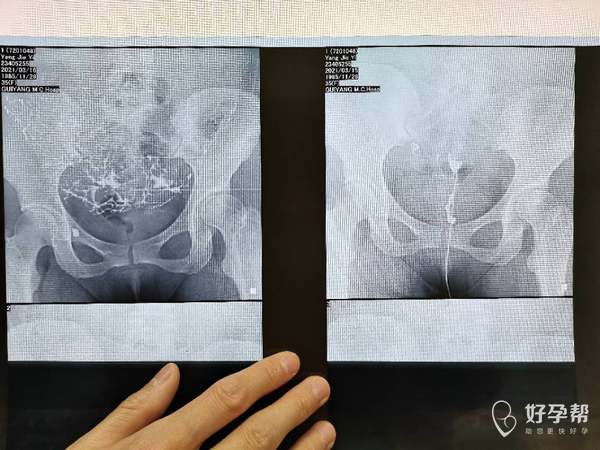

医生您好麻烦看下我的输卵管造影片影像科的报告

你的片子不是很清楚,这样看子宫没有完全显影,双侧输卵管显影,但是没有盆腔弥散有伞断粘连和盆腔粘连。右侧输卵管积水。建议直接试管助孕或者做腹腔镜联合手术疏通输卵管分解粘连。